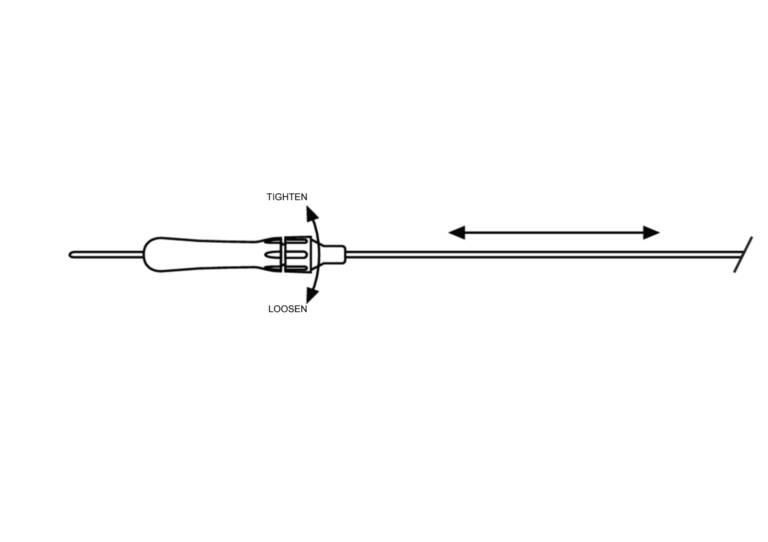

Cook® Obturator

Used to supplement and assist uterine access of a cleared, dimensionally compatible embryo transfer device for placement of in vitro fertilized (IVF) embryos into the uterine cavity.

- The adjustable length works with a variety of Cook Medical and other embryo transfer catheters.

- The hub locks in place.